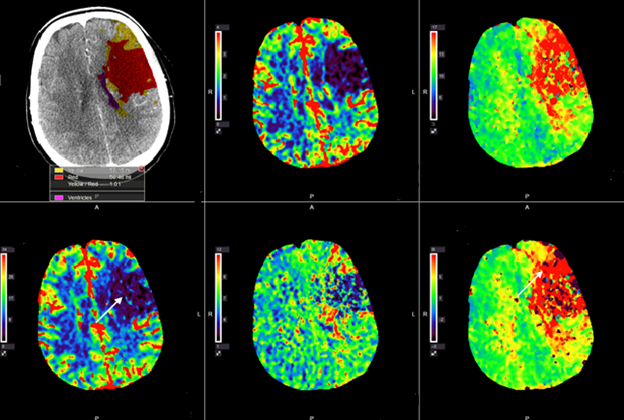

Kopš 2016. gada endovaskulāra trombektomija ir apstiprināta kā pirmās izvēles metode pacientiem ar išēmisku insultu un lielo cerebrālo artēriju oklūziju priekšējās cirkulācijas teritorijā, ja kontrindicēta intravenoza trombolīze. Šis pētījums veltīts līdz šim pietiekami neizpētītiem jautājumiem: atsevišķu ārstēšanas metožu salīdzinājumam, salīdzinot rezultātus ar kombinētas terapijas grupu (intravenoza trombolīze, kurai seko endovaskulāra trombektomija). Pētījumā vērtēti radioloģiski diagnostiskie kritēriji (piemēram, kolaterālā asinsapgāde, oklūzijas vieta, insulta plašums), kas varētu palīdzēt pacientu atlasē aktīvai ārstēšanai un sasniegt pēc iespējas labāku vēlīno klīnisko iznākumu.

Darba mērķis bija izvērtēt akūta išēmiska insulta multimodālas datortomogrāfijas diagnostikas un aktīvas ārstēšanas taktikas saistību ar radioloģisko un klīnisko iznākumu. Pētījumā tika iekļauti 288 pacienti ar akūtu išēmisku insultu pacientiem ar lielo cerebrālo asinsvadu oklūziju.

Pētījumā konstatēts, ka labam klīniskajam un radioloģiskajam iznākumam vitāli svarīga ir pacientu mērķtiecīga atlase, izmantojot tādus kritērijus kā kolaterāļu raksturojumu, potenciāli glābjamo smadzeņu audu apjomu, laiku līdz rekanalizācijai. Rezultāti arī parādīja, ka klīniskais iznākums būtiski neatšķīrās starp pacientu grupām priekšējās cirkulācijas teritorijā, salīdzinot izolētas trombektomijas vai kombinētas terapijas grupas, taču šo grupu rezultāti bija viennozīmīgi labāki nekā izolētai intravenozai trombolīzei. Savukārt pacientiem ar išēmisku insultu mugurējās cirkulācijas teritorijā kombinēta terapija uzrādīja labākus rezultātus nekā izolēta trombektomija.